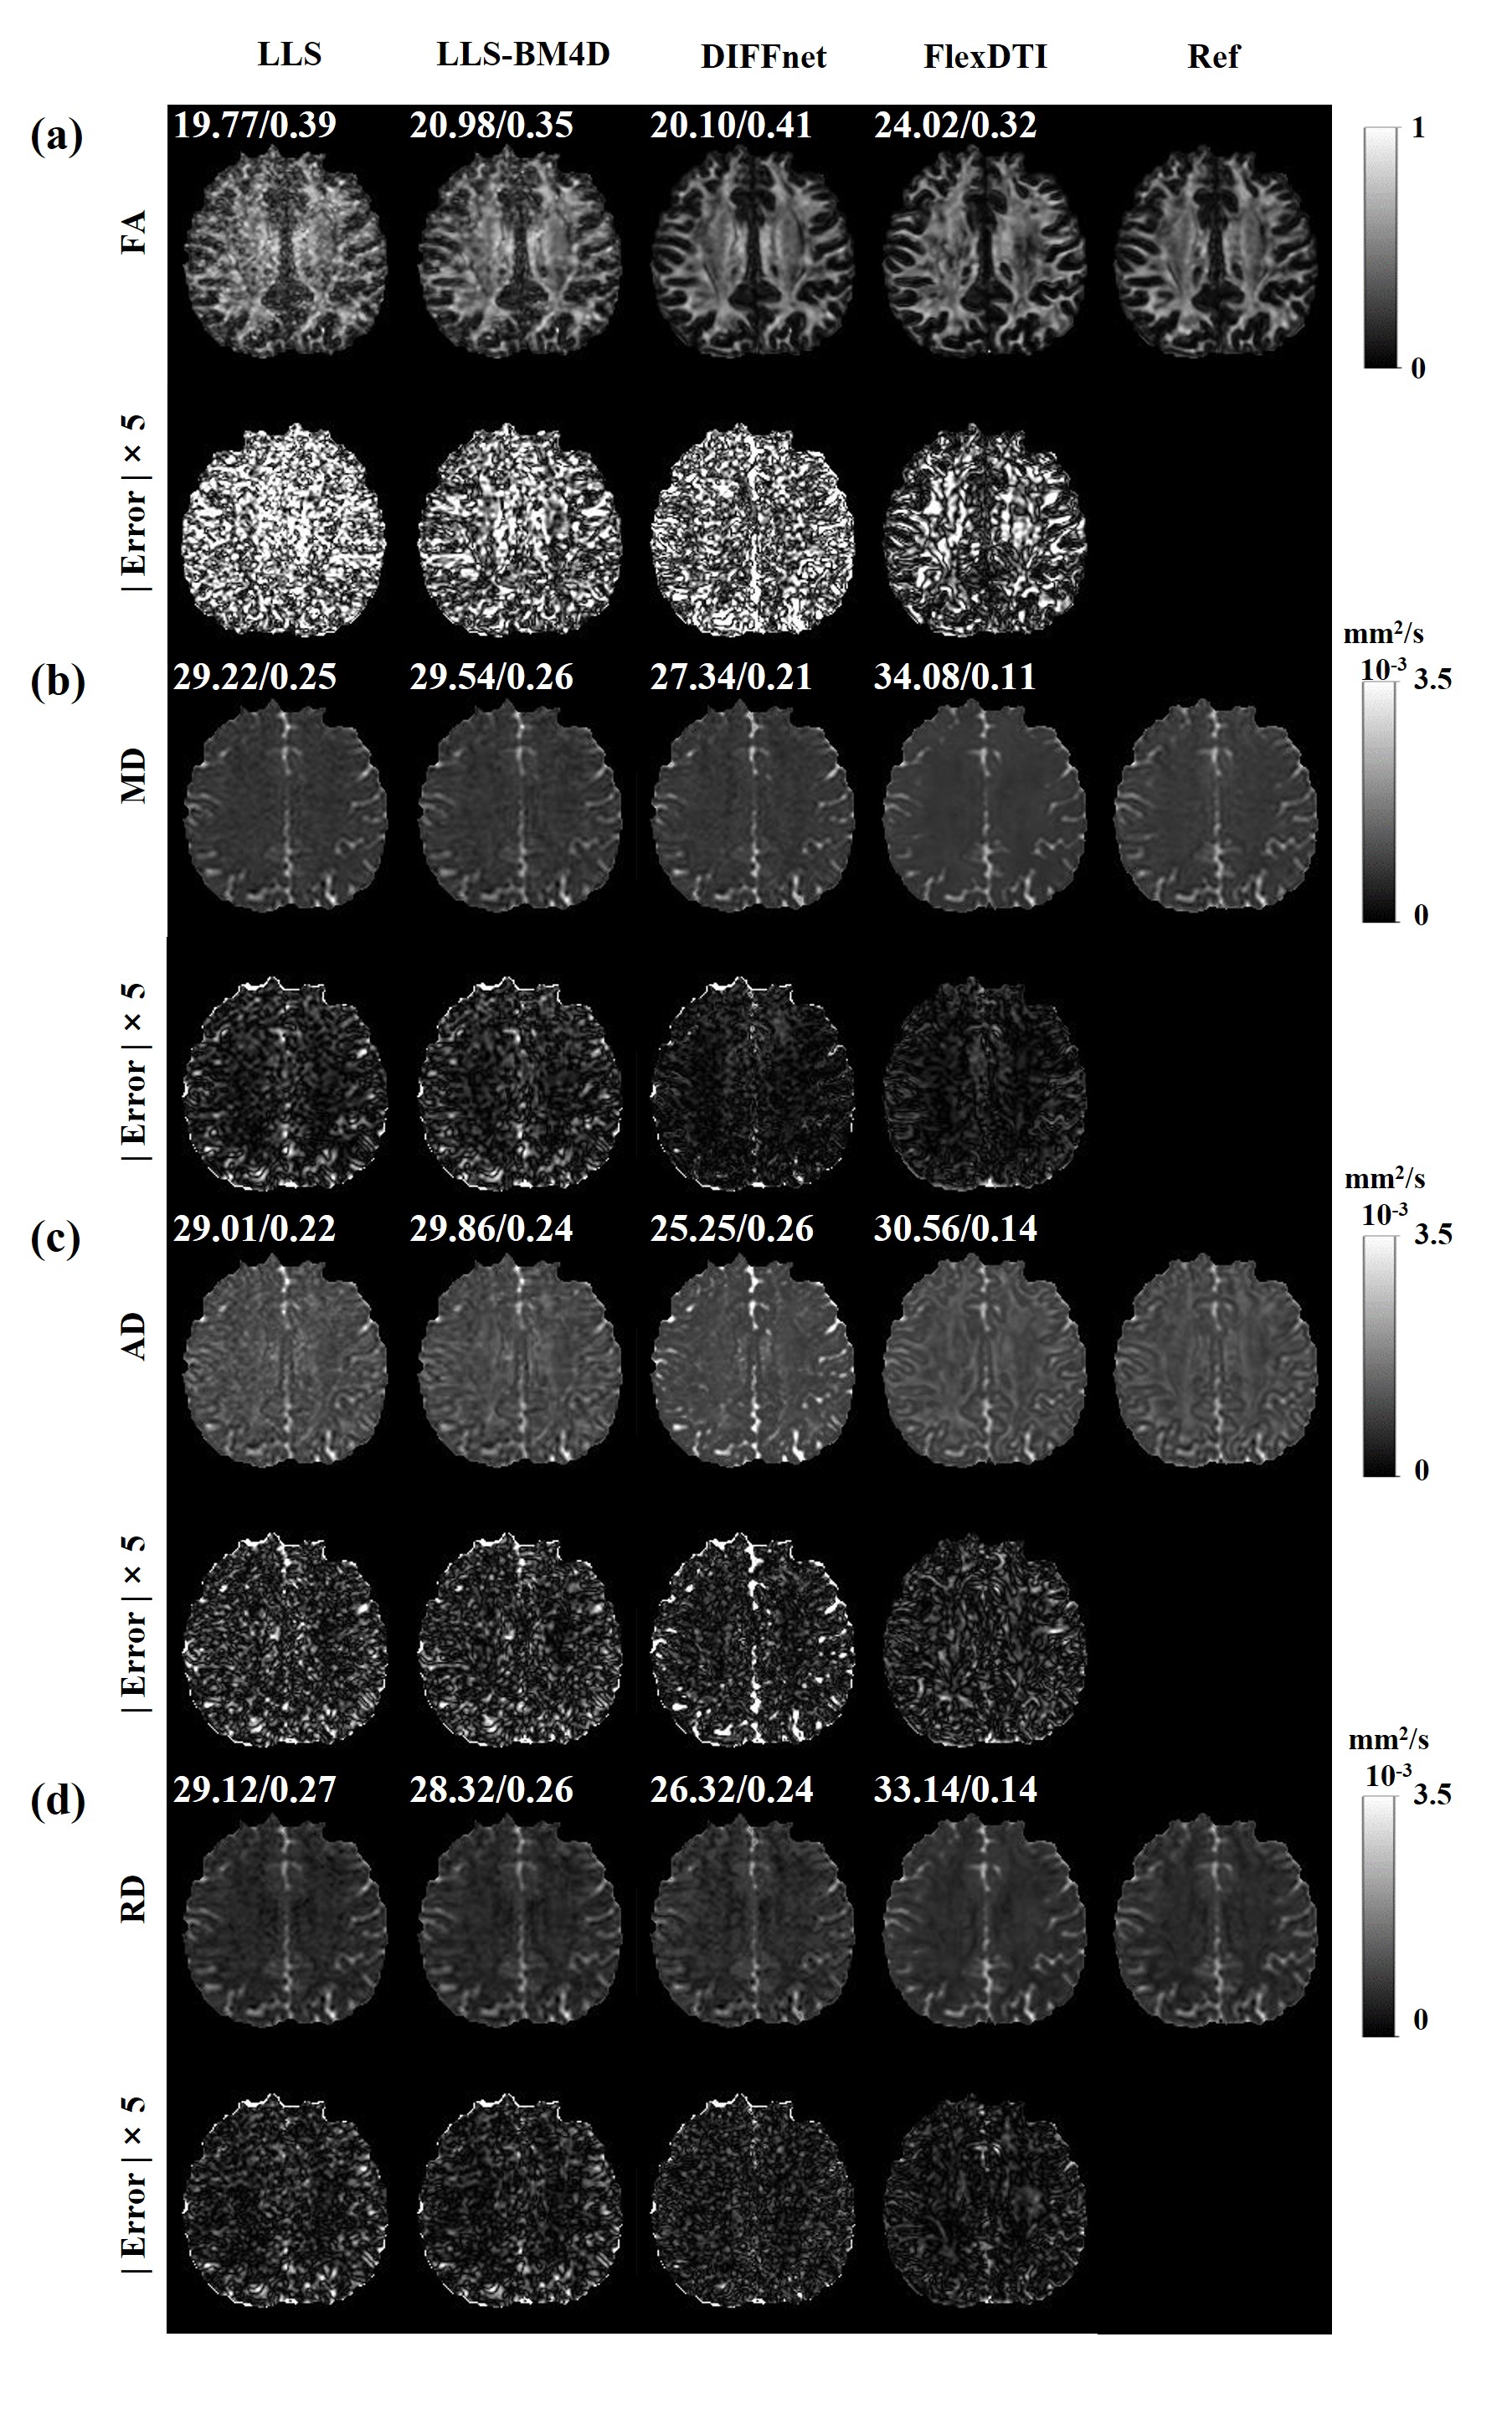

3.3 DTI reconstruction of local clinical data

Figure 5 and Table 3 show the results of further evaluations of our method on 3 test subjects from the local hospital volunteers. We used 6 DW images with flexible diffusion gradient directions to test the reconstruction effects of tensor-derived variables from the four methods. It can be observed that our method is still able to reconstruct better results than the other three methods, as demonstrated in Figure 5 and Table 3.

Figure 5: Four parametric maps (FA, MD, AD and RD) reconstructed by LLS, LLS-BM4D, DIFFnet and FlexDTI using 6 DW images with flexible diffusion gradient directions for the local dataset. The references were reconstructed by LLS using 90 DW images. The PSNRs and NRMSEs are given at the upper left corner of each reconstruction image.

The DTI reconstruction of local clinical data (Figure 5) shows that our method is suitable for different scanners, indicating its strong generalization ability. Once the network is trained, it can be used for different diffusion gradient schemes on different types of scanners, which is of great convenience for the clinical application of deep learning-based DTI. It should be pointed out that, for high-resolution DTI, mitigating local volume effects enables finer structural resolution, holding significant implications for enhancing the accuracy of DTI in clinical applications (Wu et al 2013, Liu et al 2009). However, due to its prolonged scanning time, current clinical practice often utilizes lower resolution. On a clinical MRI scanner, a more common resolution is a 2×2×2 mm3𝑚superscript𝑚3mm^{3}italic_m italic_m start_POSTSUPERSCRIPT 3 end_POSTSUPERSCRIPT acquisition. Figure 8 shows the results of further evaluations of our method on typical clinical brain MRI protocols with three healthy volunteers. Figure 9 shows the performance of FlexDTI in other scan parameters like slice thickness, TE, phase partial Fourier and parallel imaging. According to the quantitative assessment of FA, MD, AD and RD, it can be seen that the proposed method still outperforms other methods for the typical clinical brain MRI protocols and keeps stability under different scan parameters, proving that the proposed model has good generalization performance.